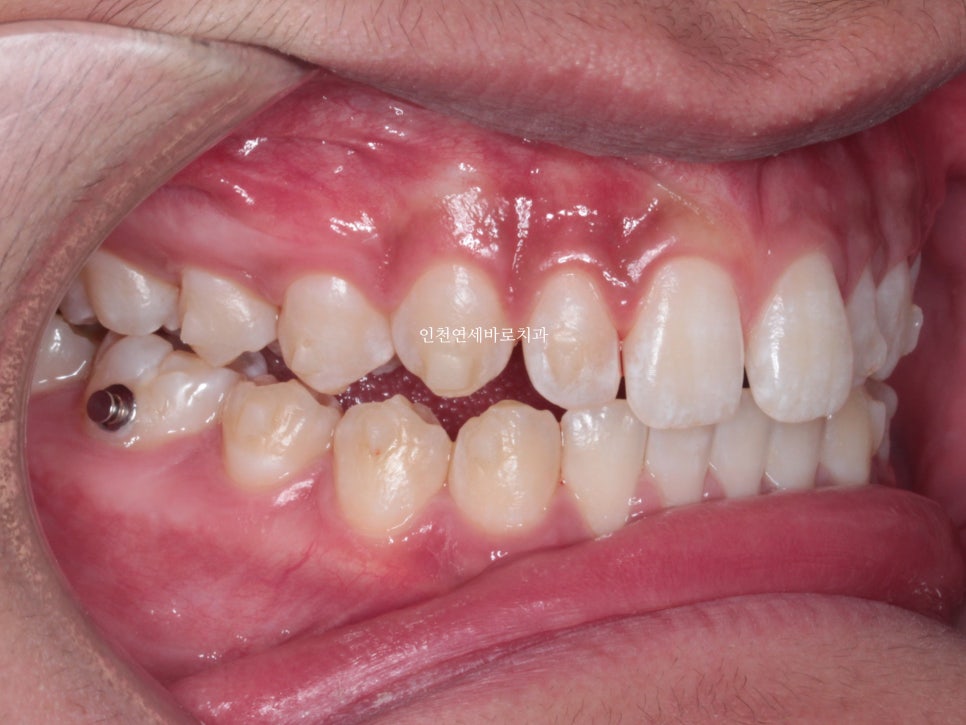

인비절라인은 플라스틱 장치를 착용하는 것으로 모든 치료가 되지 않습니다.

고무줄도 사용하여야 하며, 필요시 #미니스크류 도 식립해야 합니다.

한번의 재제작을 했던 환자분입니다.

재제작 소요기간 한달을 포함해서 환자분이 병원에 오고 딱 1년만에 치료가 마무리 되었습니다.

문제가 되었던 오른쪽 어금니 교합도 좋게 마무리 하였습니다.